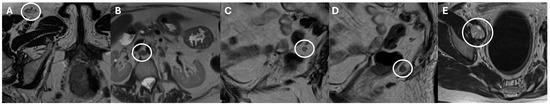

| Bai et al. [19] | Retrospective | MRI | 216/216 | Renal cell carcinoma |

|